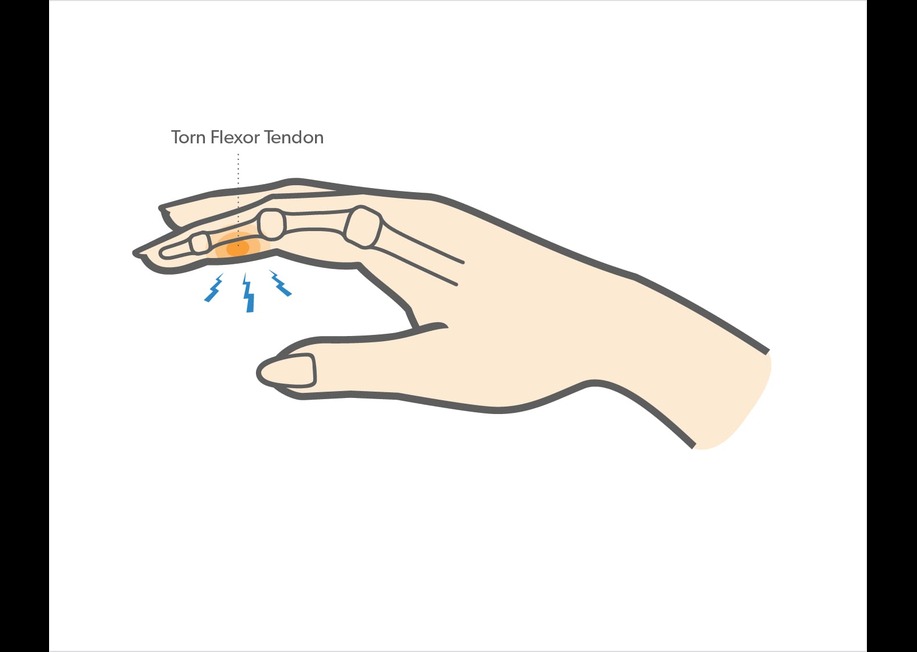

پارگی یا کنده شدن(avulsion) تاندون عضله فلکسور عمقی انگشتان (Flexor digitorum profundus ) که اصطلاحا به آن انگشت جرسی (jersey Finger ) می گویند می تواند در همه انگشتان اتفاق بیافتد ، اما در انگشت حلقه شایع تر است.

این آسیب معمولاً زمانی اتفاق میافتد که فشاری بیش از حد به انگشت خم شده اعمال میشود، زیرا در این حالت بند آخر انگشت که به صورت ارادی خم شده ناگهان با یک نیروی شدید و ناگهانی صاف شده ( اکستند شده) و باعث پارگی یا کنده شدن این تاندون در محل اتصال خودش به آخرین بند انگشت(distal phalanx)می شود.